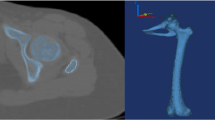

In this paper, numerical modeling and analysis of a HA-coated PEEK/Ti macro-composite hip stem is presented. The macro-composite hip stem consists of a titanium core in the center and a PEEK layer around it and a thin HA coating on the surface. The composite stem was designed and implanted in a standardized human femur bone model in SolidWorks software. The intact and postoperative femur bones were loaded like as in the single-leg stance of the walking gait and the effect of PEEK layer thickness on the internal stresses was analyzed in ANSYS software. Results were compared with an all-metallic stem model. Also, the fatigue strength of the stem and stresses occurring in the implant/coating interface were analyzed. With the composite stem, more homogeneous load distribution could be achieved, thus the stress-shielding effect was considerably reduced. Composite implants with 2 and 3 mm of PEEK layer provided sufficient fatigue strength in accordance with ASTM F2996-13 and ISO 7206-4:2010 standards. Maximum stresses at the coating/implant interface were well below the plasma-sprayed HA coatings strengths on PEEK implants. It is thought that the designed composite model may be an alternative to the standard HA-coated Ti alloy hip implants.